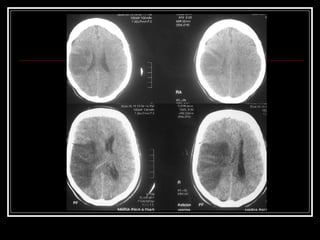

Exames de Imagem Qual a primeira escolha na emergência? Por quê? Qual o método mais sensível?

Exames de ImagemQual a primeira escolha na emergência? Por quê? Qual o método mais sensível?

Diagnóstico Diferencial Enxaqueca Paresia pós-ictal Hipoglicemia Conversão Hematoma subdural Tumores cerebrais Encefalopatia hipertensiva AVE isquêmico vs. hemorrágico AIT Encefalopatia metabólica

Diagnóstico Diferencial EnxaquecaParesia pós-ictal Hipoglicemia Conversão Hematoma subdural Tumores cerebrais Encefalopatia hipertensiva AVE isquêmico vs. hemorrágico AIT Encefalopatia metabólica